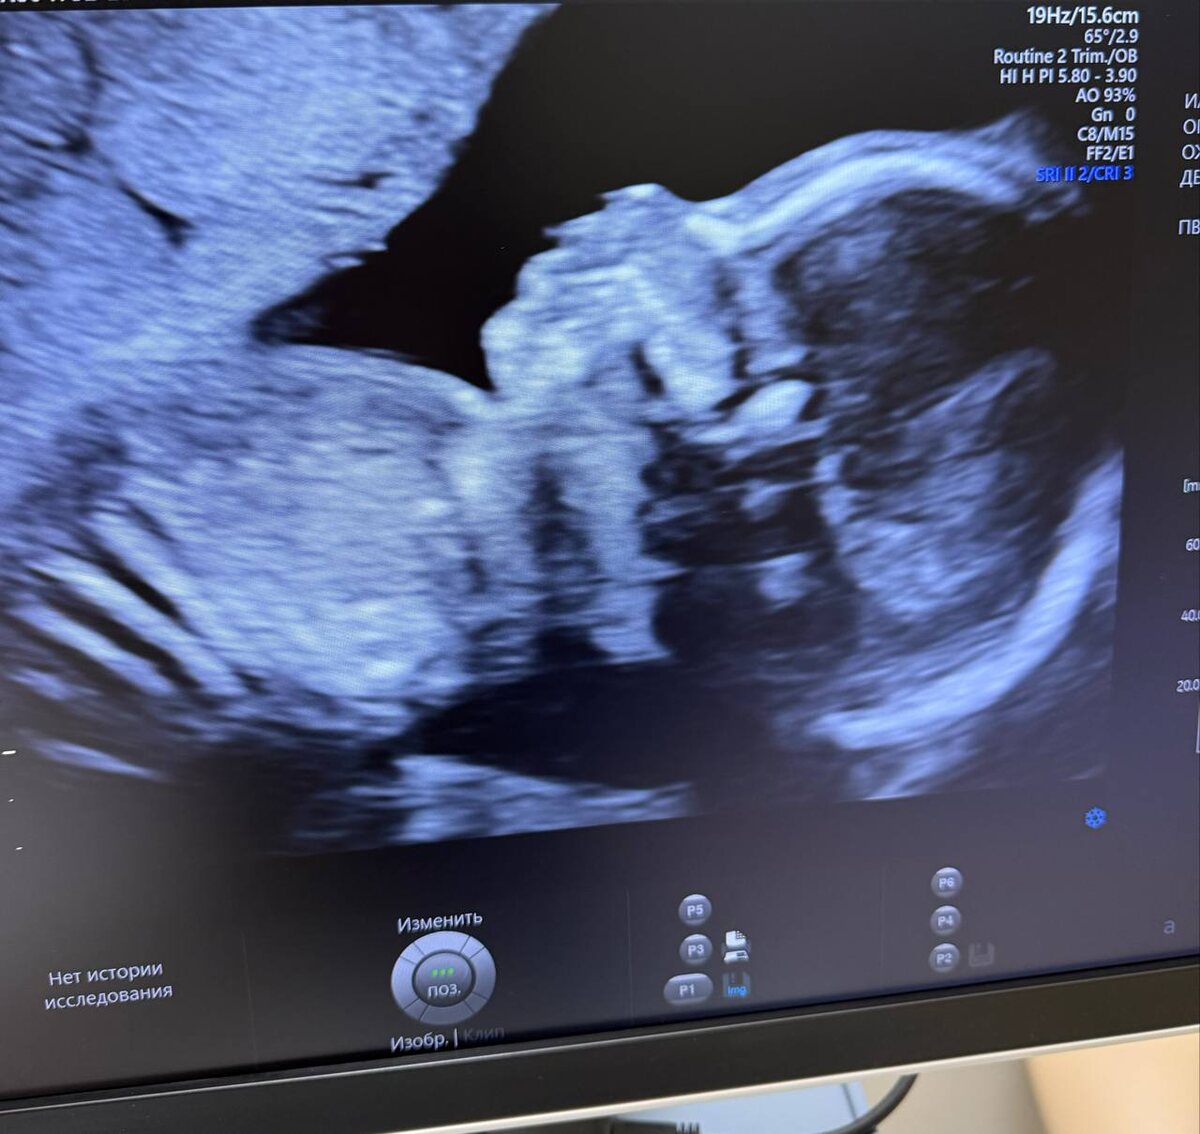

Сегодня был второй скрининг. С ребенком все хорошо! Весит 307 грамм. Врач сказал, что такого веселья у него на узи еще не было 😄 Ловили человека по всему животу) Еще и ручками лицо постоянно было закрыто) Нам подтвердили пол! У нас будет девочка 🫶 Лиза оказалась права)